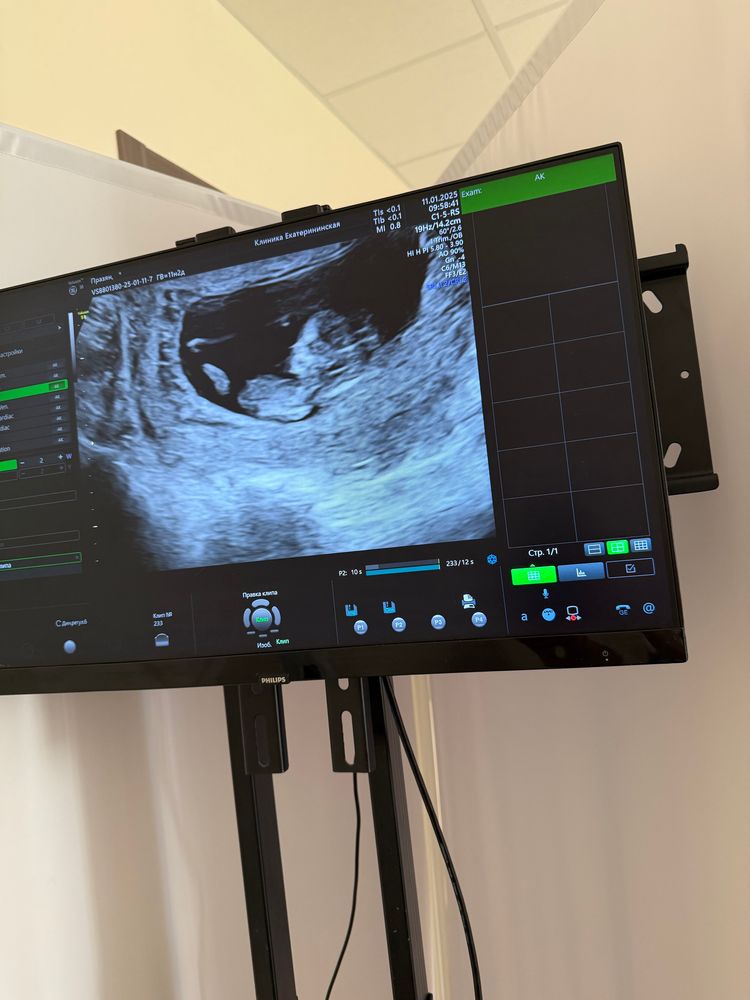

Узи в 11 недель 1 день

Девочки, пошла я просто на узи ( не скрининг) для своего спокойствия, у нас все хорошо, растет малыш)))срок чуть больше по ктр у нас 11,5 дней, ктр 49 мм, чсс 165. Сделала пару фото с видео как думаете кто у меня? 🥹

по фото конечно качество не очень 😅 а видео вставить не могу)

El M, я и не сомневалась☺️, под писюшкой бубенчики видны🫣.

El M, вот в кружочек обвела писюшку с яйками малыша, а сверху эта пуповина🙂